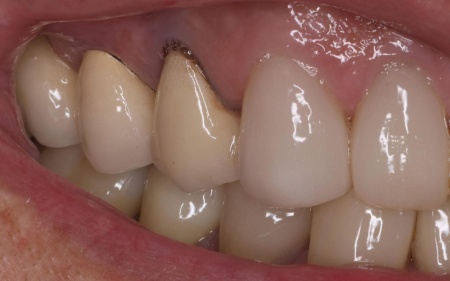

| 主訴 | 「被せ物の根元が黒くなっているのが気になる」とご相談いただきました。 |

| 診断 | 拝見したところ、右上4番目の歯には白い被せ物が入っていましたが、加齢により歯ぐきが下がったことで被せ物が合わなくなり、土台が見えて黒くなっていました。

この歯は笑ったときに見えやすい部分のため審美性に影響が出ており、さらにこのまま放置すると隙間から細菌が入り込んで虫歯が再発するリスクもあります。 以上のことから、被せ物を取り外し新しい被せ物に交換する必要があると診断しました。 |

治療前